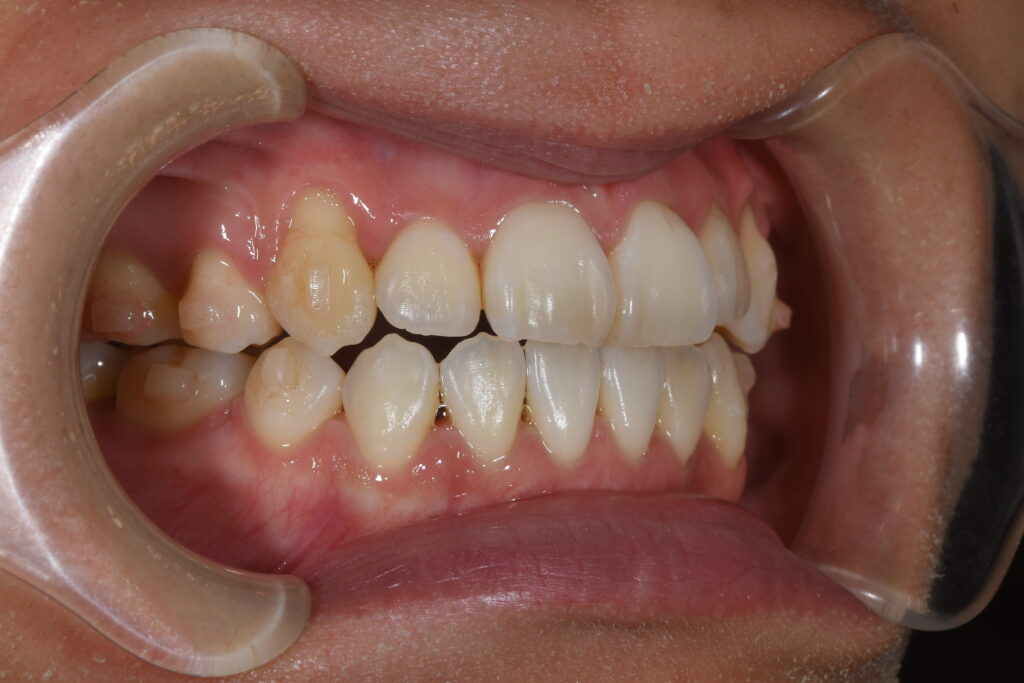

矯正開始1年の状態です。

【治療開始1年】

開口・抜歯矯正と治療難易度は高いですが、患者様がしっかりとマウスピースを装着して頂けているのもあり、1年でここまでの状態に改善しております(^^♪(もちろん、この状態から最終の状態へもうしばらく治療は必要です!)

矯正治療において、どうしてもスペースがなければ抜歯が必要になるケースもありますが、インビザライン矯正(マウスピース矯正)でここまでかみ合わせもしっかり改善することが可能になります。